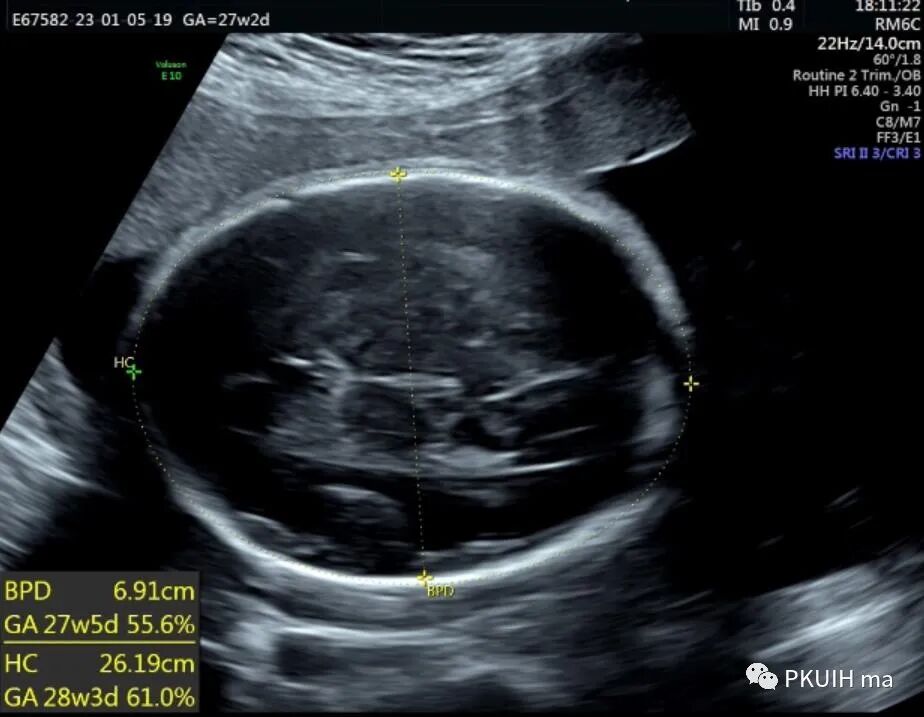

孕妇26岁,G2P0,发现胎儿肢体异常来诊,目前孕27周,超声图像如下:

产前诊断主要依靠超声或核磁,出生后主要依靠X线和螺旋CT。超声检查建议采用连续顺序追踪法来观察胎儿肢体,如果怀疑有骨骼疾病应进行完整的胎儿超声评估,包括胎儿胎儿运动的评估。当有骨骼发育不全家族史时,应对以下超声征象仔细评估:完整的生物学测量,包括BPD、HC、AC,所有长骨的长度,股骨/足底比值,和下颌骨、锁骨、肩胛骨、颅骨、胸廓和脊柱的观察或测量。其他可能有助于鉴别骨骼发育不良的超声参数包括胎儿面部轮廓(比如鼻骨扁平)、椎体是否存在及形状、手和足的外观(比如多指(趾)、缺指(趾)或指(趾)畸形)和用来评估致死性风险的胎儿胸部。有研究显示FL/AC比值小于0.16是致死性骨骼发育不良胎儿的主要鉴别要点,并且该测值比股骨短、胸围、胸围/腹围更有效。